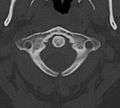

Axis seen from above.